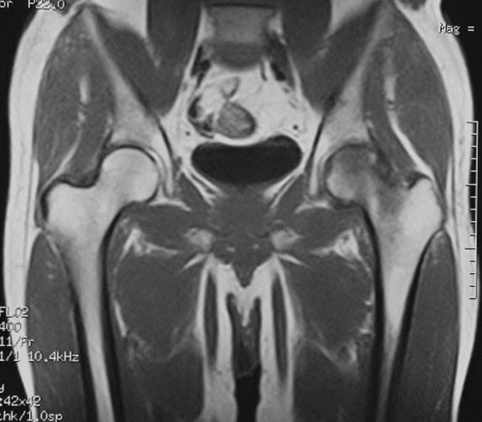

Показания для проведения МРТ тазобедренных суставов:

- постоянные боли в области сустава;

- боли вследствие травматических повреждений;

- отек сустава;

- переломы;

- вывихи;

- растяжения;

- нарушение подвижности и онемение.

Как проводится МРТ тазобедренных суставов?

Перед укладкой в томограф необходимо снять все металлические предметы. После этого пациент ложится на стол сканера, который постепенно перемещается в аппарат. Во время сканирования следует лежать неподвижно, чтобы получаемые изображения были четкими и неискаженными.